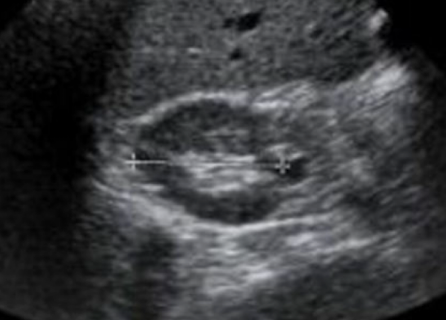

What section of the kidney is this and which scan plane?

Transverse midpole (has a horseshoe shape)